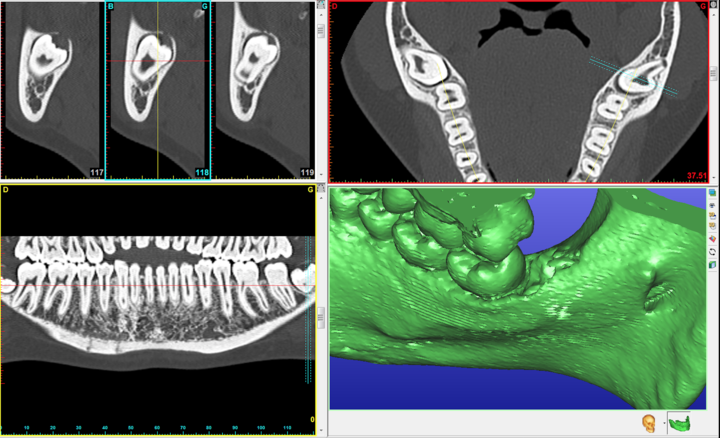

L’extraction des dents de sagesse consiste à enlever les troisièmes molaires du haut et/ou du bas. Chez l’enfant ou l’adolescent, ces dents n’ont pas terminé leur développement et sont appelés germes (l’intervention est appelée « germectomie »).

Ces dents doivent être extraites parce qu’elles sont en mauvaise position et sont à l’origine de douleurs et d’inflammation ou parce qu’elles risquent de perturber le bon alignement des dents chez l’enfant ou l’adolescent (l’indication est souvent portée par l’orthodontiste) .

• une diminution ou une modification de la sensibilité de la lèvre inférieure ou plus rarement de la langue car les nerfs cheminent à proximité de la dent et peuvent être irrités. Ce trouble de la sensibilité est temporaire (quelques jours à quelques semaines), mais dans certains cas, la récupération peut être très longue (1 à 2 ans). Ce trouble est très exceptionnellement permanent.

• l’expulsion de la dent de sagesse supérieure en haut dans le sinus maxillaire ou en arrière de celui-ci est très rare mais peut justifier une nouvelle intervention chirurgicale pour la récupérer.